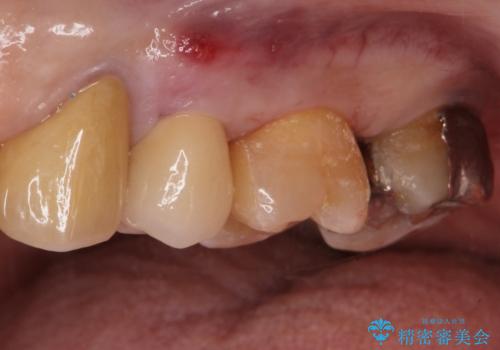

銀歯を除去し隣の歯も虫歯が見られたのでジルコニアクラウン、e-maxインレーで治療を行いました。

適合の良い被せ物、詰め物が入りました。

今後被せ物、詰め物が欠けたりしないようにナイトガードの使用をお勧めしています。